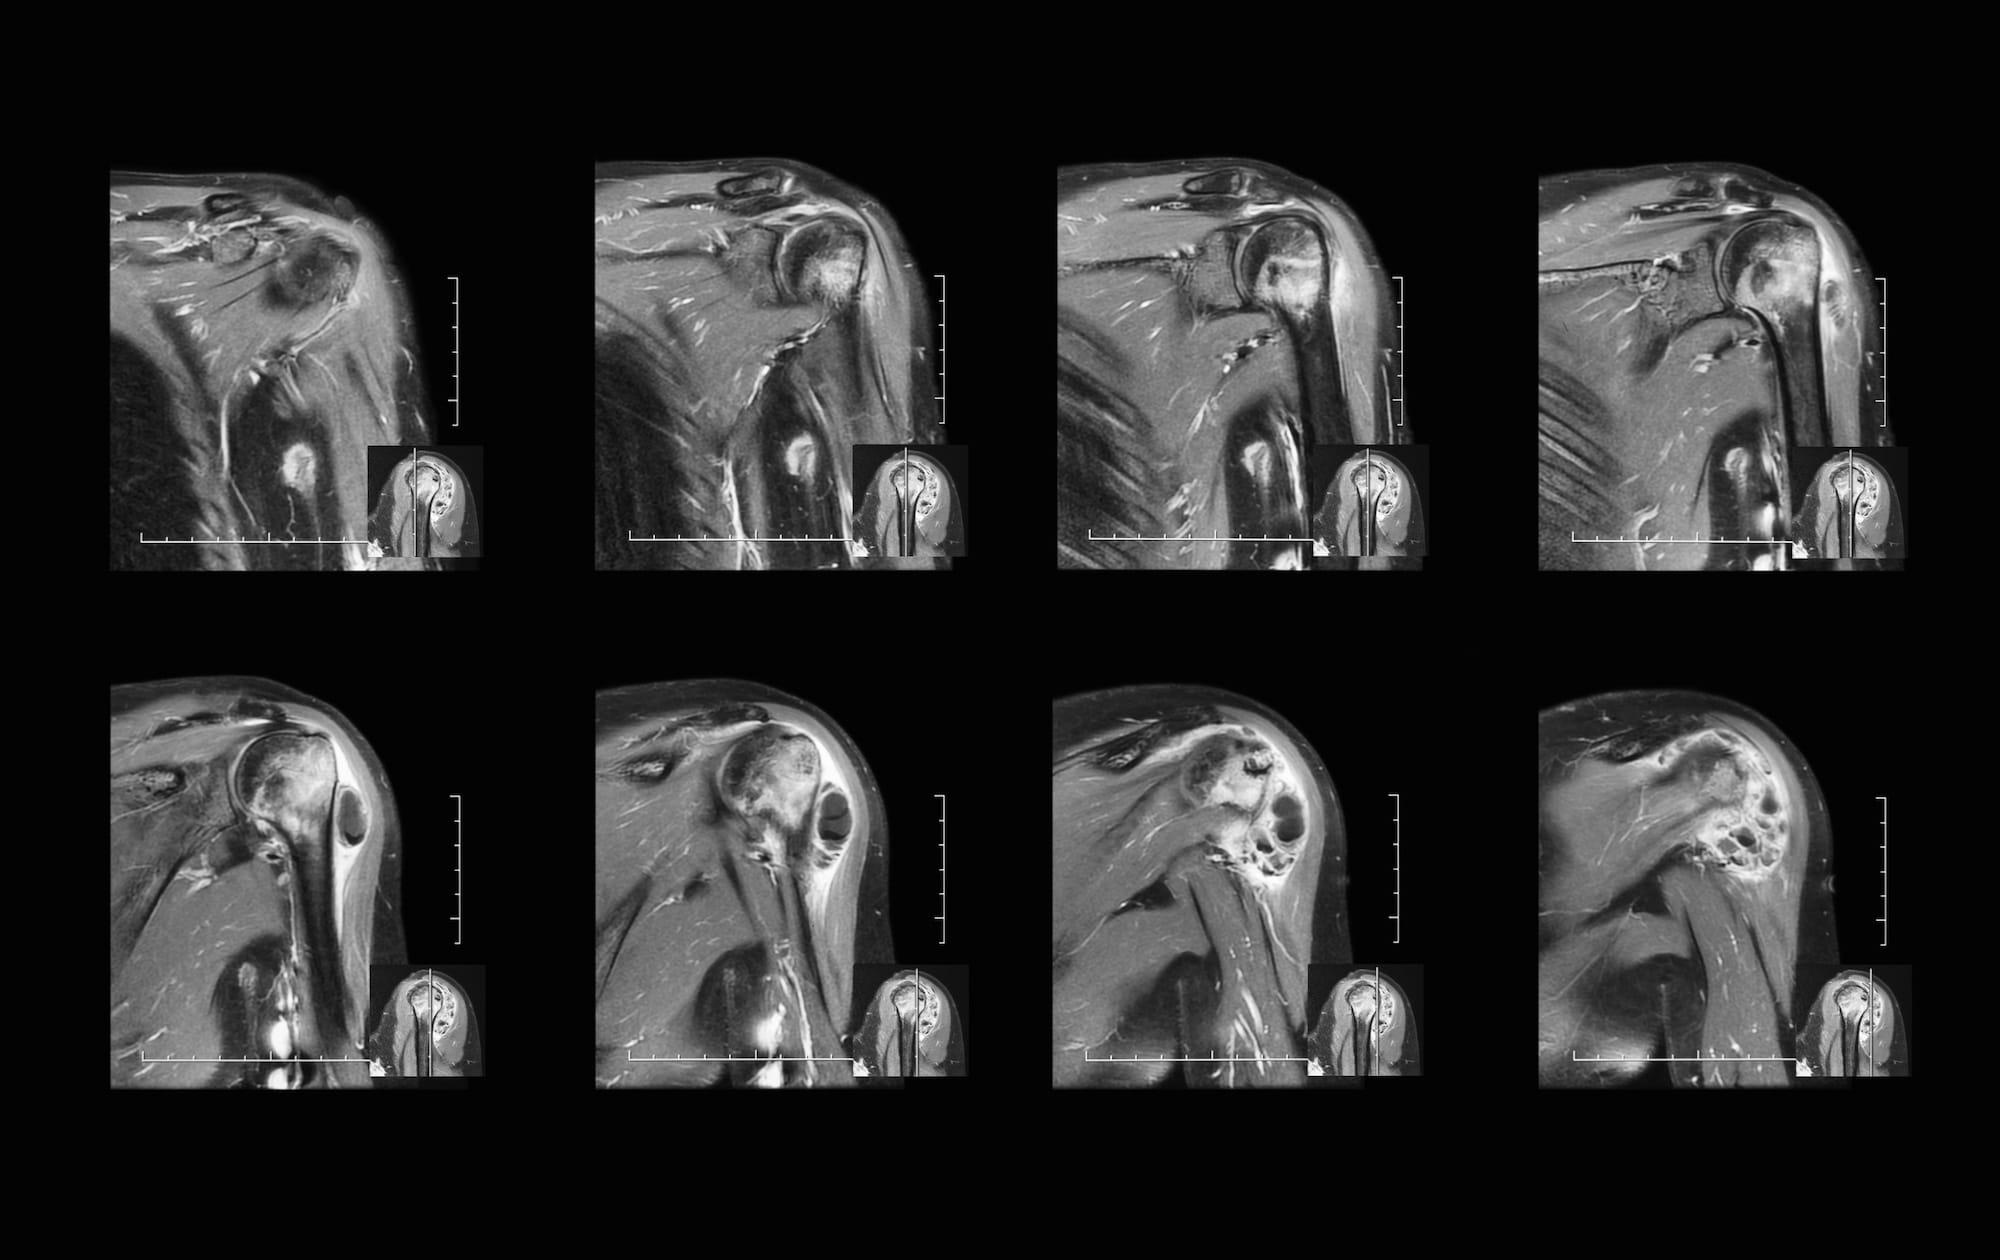

Shoulder MR arthrogram 31M with pain 6 weeks after fall OCAD What Is An Mri Arthrogram Shoulder These tests can show ligament,. The shoulder joint is a joint that connects the upper limb to the axial skeleton. Learn how it works, when you might need. The procedure is often followed by a ct or. What is a shoulder mri scan? An mri scan uses magnets and radio waves to capture images of your body’s internal. Learn more. What Is An Mri Arthrogram Shoulder.

Normal MR arthrogram axial T1weighed FS (a) and sagittal T1weighted What Is An Mri Arthrogram Shoulder Learn more about this procedure. Mri shoulder arthrography is typically ordered to assess anatomical structures poorly visualized without the. The procedure is often followed by a ct or. An mri scan uses magnets and radio waves to capture images of your body’s internal. What is a shoulder mri scan? It is composed of two articulations; Mri arthrography uses magnetic resonance. What Is An Mri Arthrogram Shoulder.